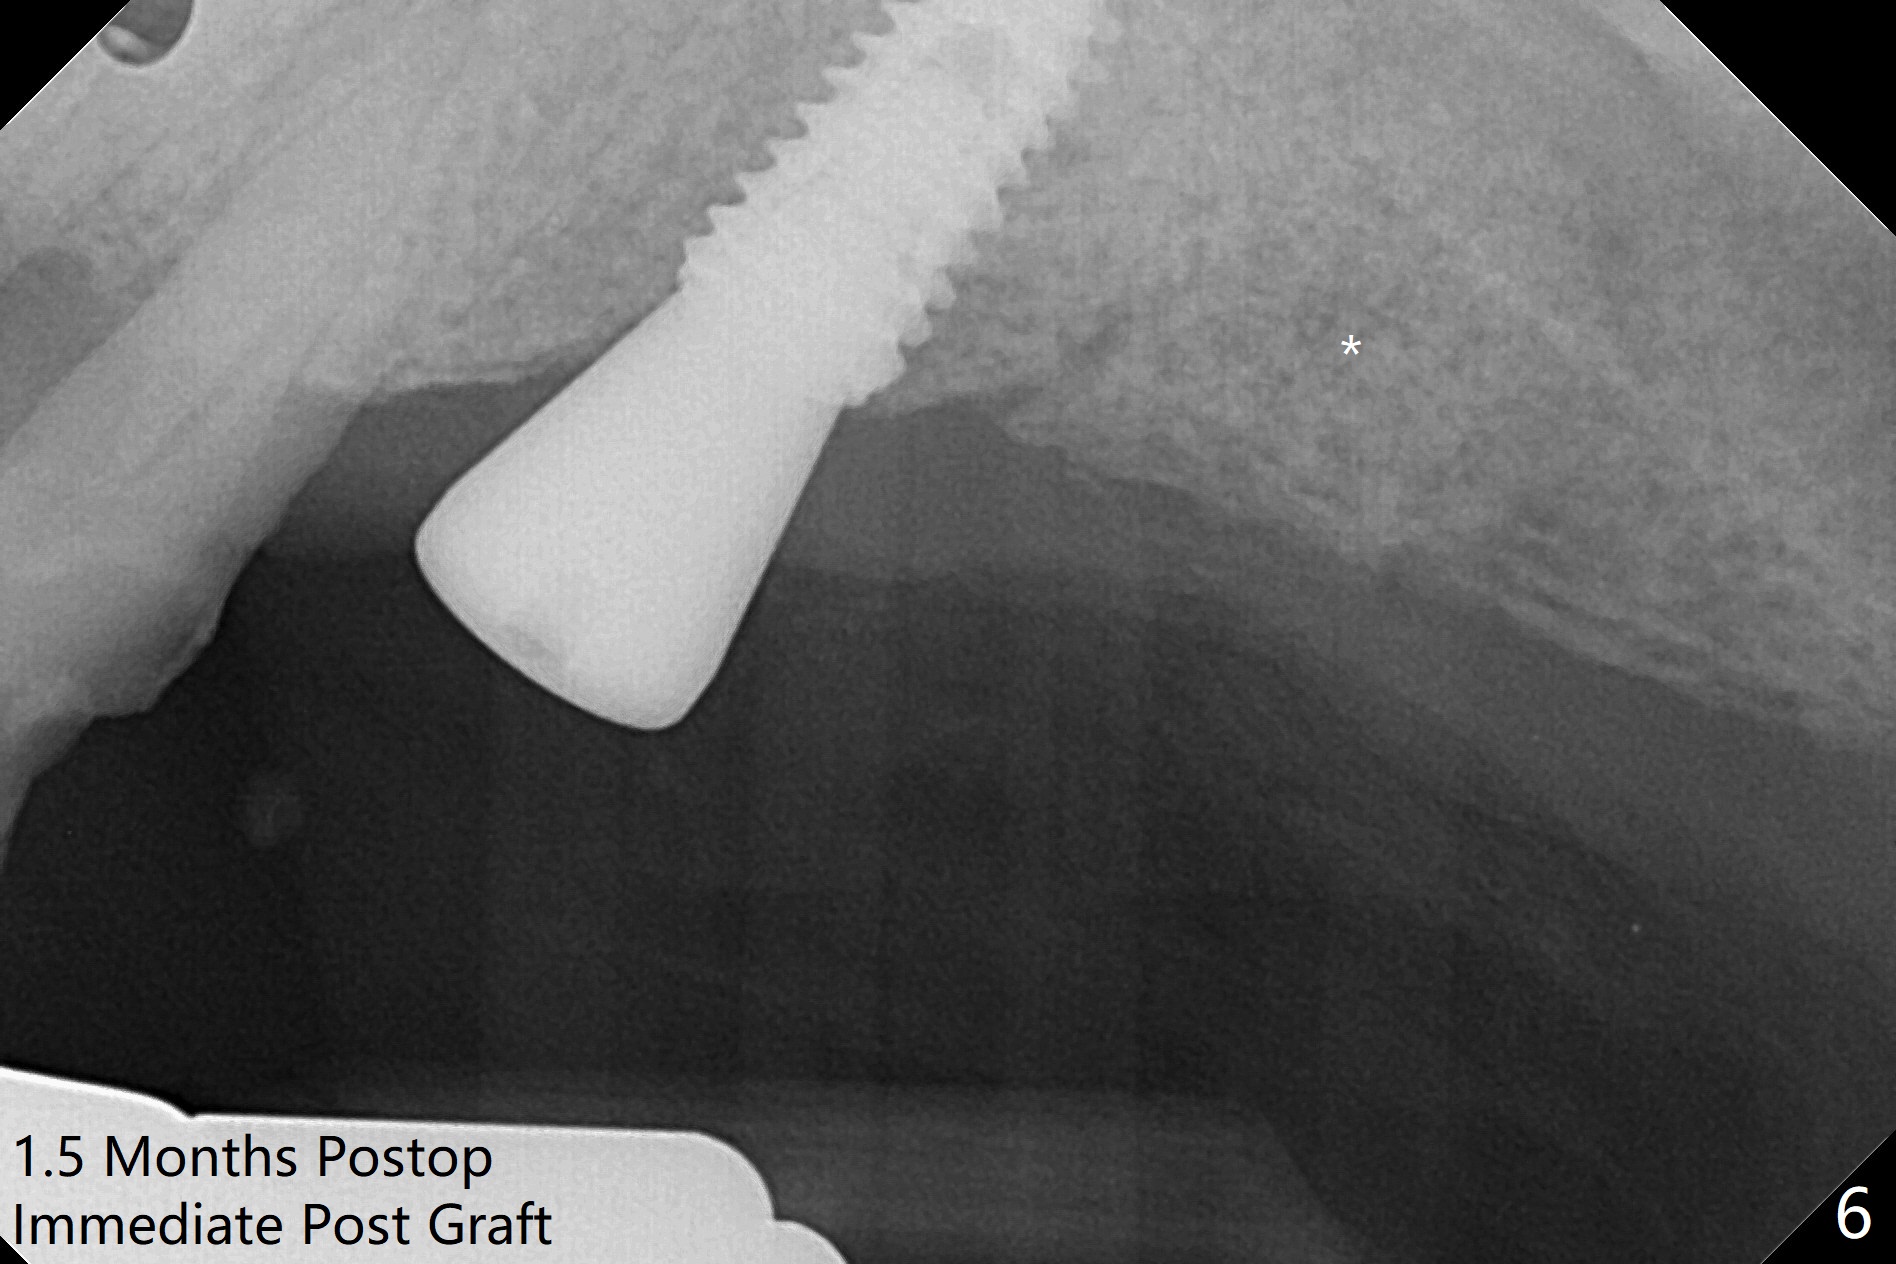

PA is taken after 2.2 mm drill reaches the depth at #13 to confirm that the osteotomy is parallel to the long axis of the tooth #12 (Fig.1). Fixture mount is used to place a 4x10 mm implant at #13 and stays as an anchor pin while osteotomy and sinus lift are being conducted at #14 (Fig.2). In fact there is discrepancy in depth using the guide. For example the last drill for osteotomy is 4.5x7.3 mm according to design, whereas 4.5x11.5 mm drill has to be used before the sinus floor has small area of perforation without sinus membrane breakage. Autogenous bone harvested from the osteotomy, PRF membrane and a 4.5x10 mm dummy implant are used for sinus lift (Fig.2). The placement depth of the implant at #13 has to be adjusted multiple times until satisfaction (Fig.2-5). The implant at #14 is infected and loosened 1.5 months postop; after its removal, the sinus floor is absent without membrane perforation; the large defect with basically intact buccal and palatal walls is grafted (Fig.6 *). Four to five months later, use the same guide and drill sequence until 3.5x7.3 mm drill. Insert a 4x10 mm dummy implant to the 2nd line of 12 mm offset and take 5x5 cm CT to determine the diameter and depth of a final implant. Use healing screw. The pattern of bone graft changes 3 months postop (Fig.7, as compared to Fig.6). Return to Upper Arch Immediate Implant, Trajectory II 矫正,糖尿病,种植水平 Xin Wei, DDS, PhD, MS 1st edition 08/06/2019, last revision 12/06/2020